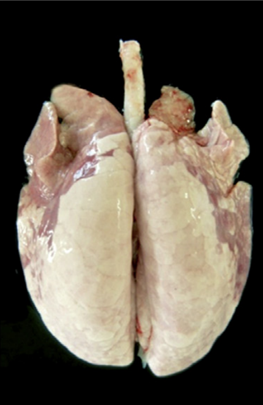

La presencia de la infección generalmente se confirma mediante la seroconversión específica a M. hyo o por la detección del agente mediante PCR en hisopos laríngeos (Pieters et al., 2017; Sibila et al., 2009). El tejido pulmonar infectado con M. hyo desarrolla consolidación y bronconeumonía catarral, con regiones de color púrpura a gris y aspecto carnoso. La consolidación puede observarse entre las 3 y 12 semanas posteriores a la infección. Las lesiones se localizan principalmente en los lóbulos apicales y cardíacos, así como en la parte anterior de los lóbulos diafragmáticos y en el lóbulo intermedio. Las lesiones se resuelven entre las 12 y 14 semanas, dejando como secuela la formación de fisuras interlobulares (Maes et al., 2008). Dado el carácter crónico de este tipo de lesiones, la bronconeumonía con consolidación cranioventral de los pulmones es muy indicativa de NE, incluso en cerdos de abasto.

Ejemplo de un pulmón con lesiones derivadas de una inoculación experimental de M. hyo (García-Morante, 2016).